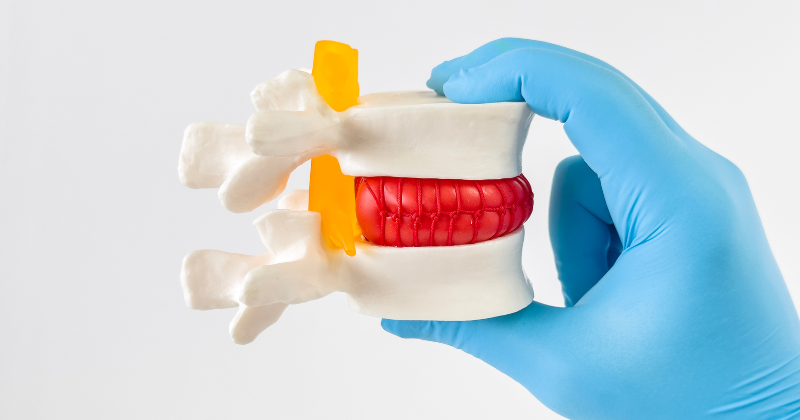

Walken, Schwimmen, Yoga – diese Sportarten sind nach einem Bandscheibenvorfall geeignet

Etwa 80 Prozent der Deutschen sind mindestens einmal in ihrem Leben wegen Rückenbeschwerden in ärztlicher Behandlung. Häufig kann ein Bandscheibenvorfall die Ursache für die Schmerzen sein. Über Definition, Häufigkeit und verschiedenen Therapieformen informieren wir im Folgenden. Darüber hinaus wird der Frage nachgegangen, ob Sport bei ...

Die Bandscheibenvorwölbung: Ursachen, Symptome, Diagnose und Behandlungsmöglichkeiten

Viele Menschen sind von Rückenschmerzen betroffen. Oft steckt dahinter eine Bandscheibenvorwölbung. Sie kann symptomfrei verlaufen oder starke Schmerzen auslösen. Um einen Bandscheibenvorfall zu vermeiden sollte die Vorwölbung mit den richtigen Therpien behandelt werden.